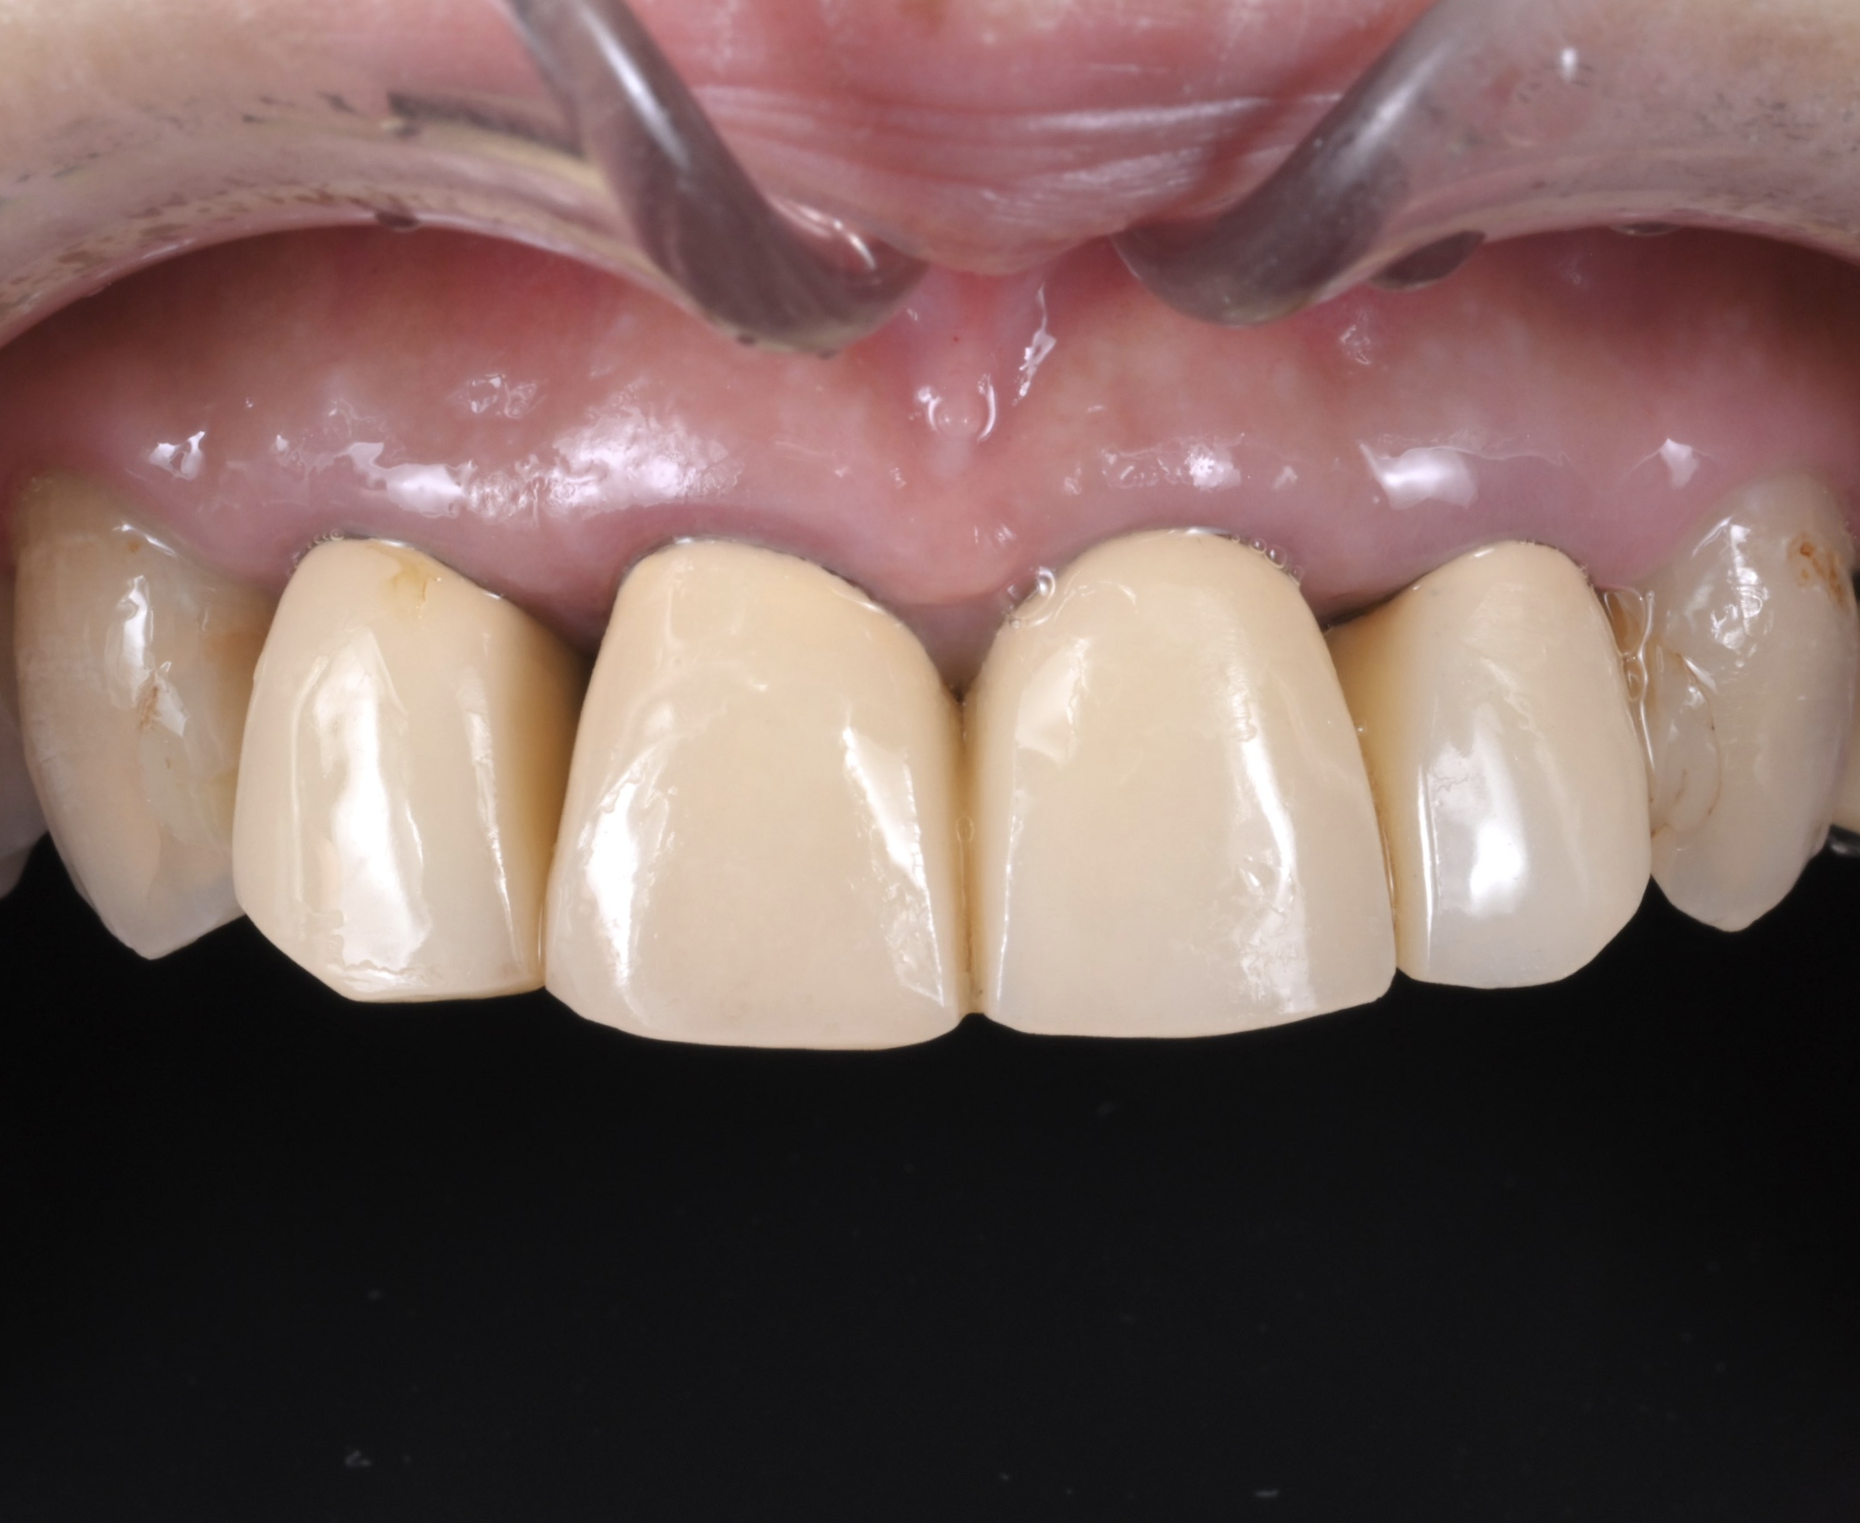

治療前

口腔内写真